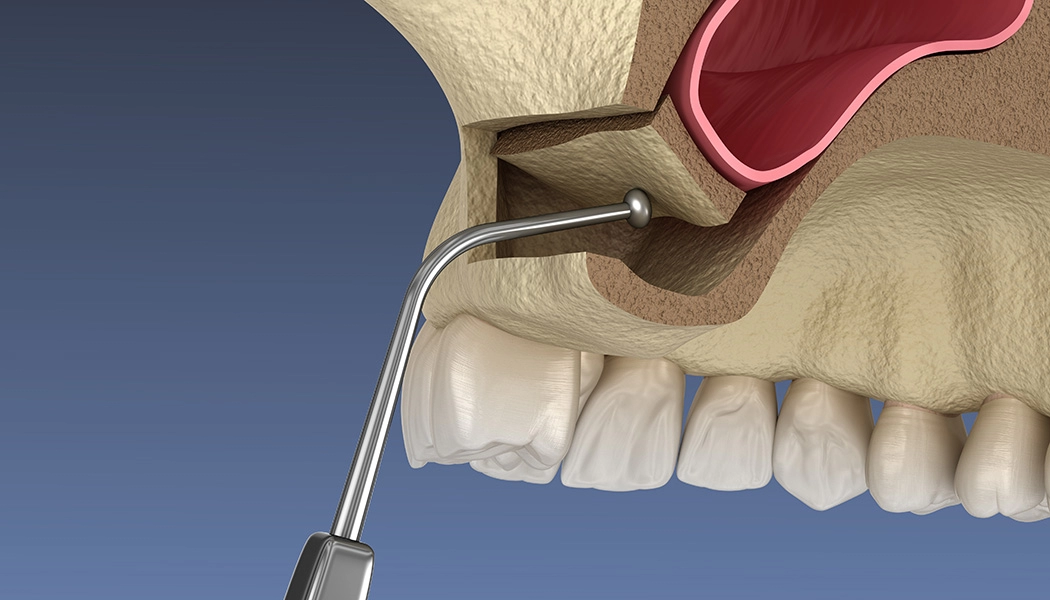

Расщепление альвеолярных отростков проводят путём механического расширения стенок гребня и заполнения образовавшейся полости костным материалом. За счет этого компенсируется нехватка ширины кости. Выполняется одномоментно с установкой имплантатов. После проведения имплантации и подсадки костной ткани десна ушивается. Метод применяется на нижней челюсти и на верхней для фронтальной зоны. При сильной вертикальной атрофии кости (нехватка высоты гребня) метод не применяется.